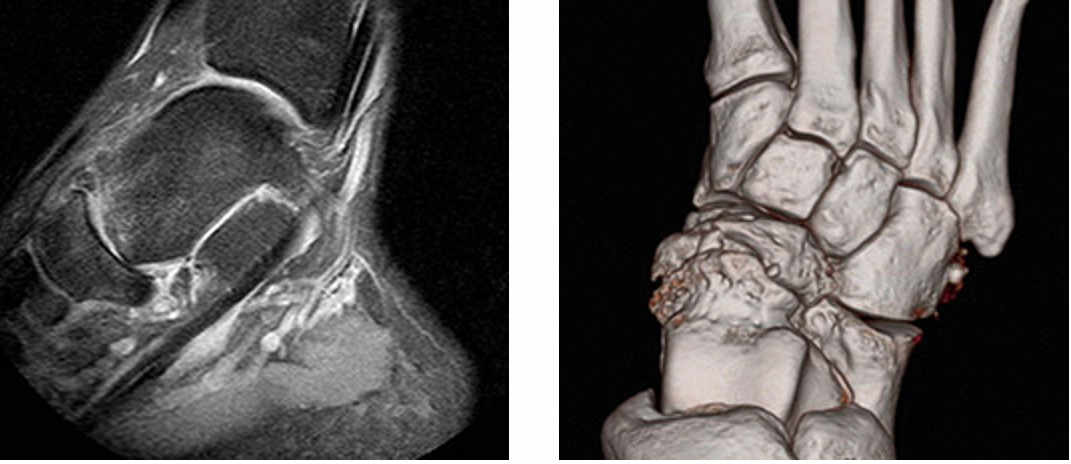

Es de gran utilidad el estudio de Resonancia Magnética del pie para valorar en detalle los huesos afectados, los tendones circundantes, así como las otras articulaciones circundantes.

En los casos susceptibles de cirugía el scanner o TAC es de gran utilidad, obteniéndose en la actualidad reconstrucciones 3D de los huesos y articulaciones del pie.